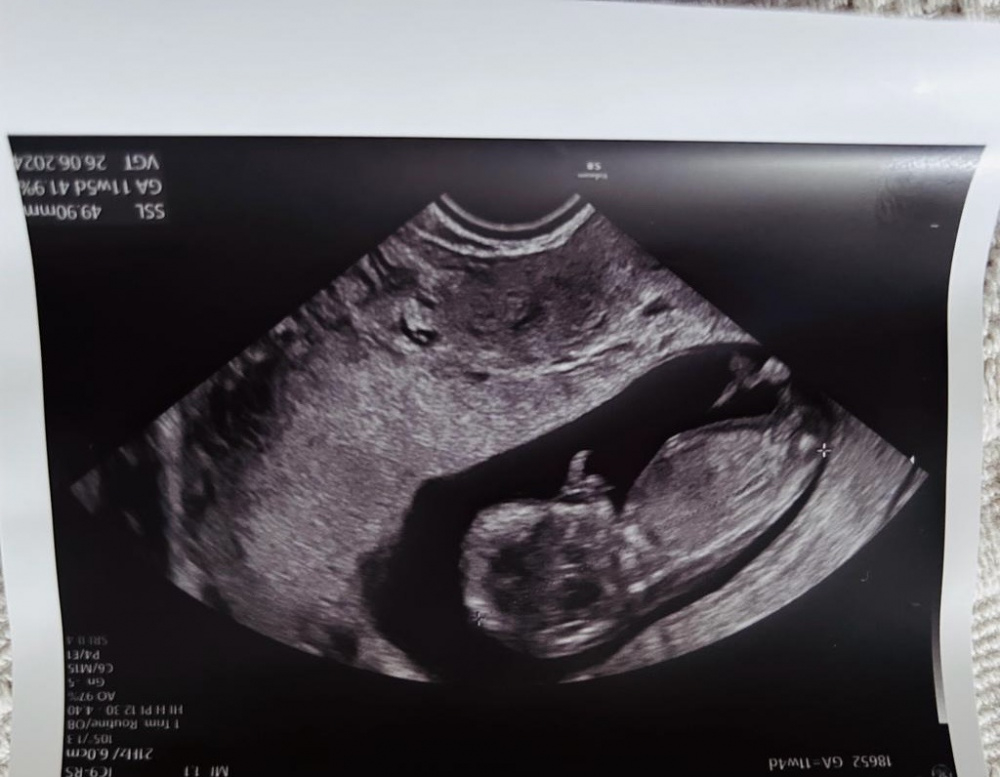

Ultraschall von oben - 2 Striche Mädel oder Bub?

Hallo Zusammen, das Bild ist in der 12. SSW entstanden. Man schaut von oben auf unseren Krümel. Es sind zwei sehr deutliche Striche. Jemand Erfahrung ob dies eher Mädchen oder Junge ist?